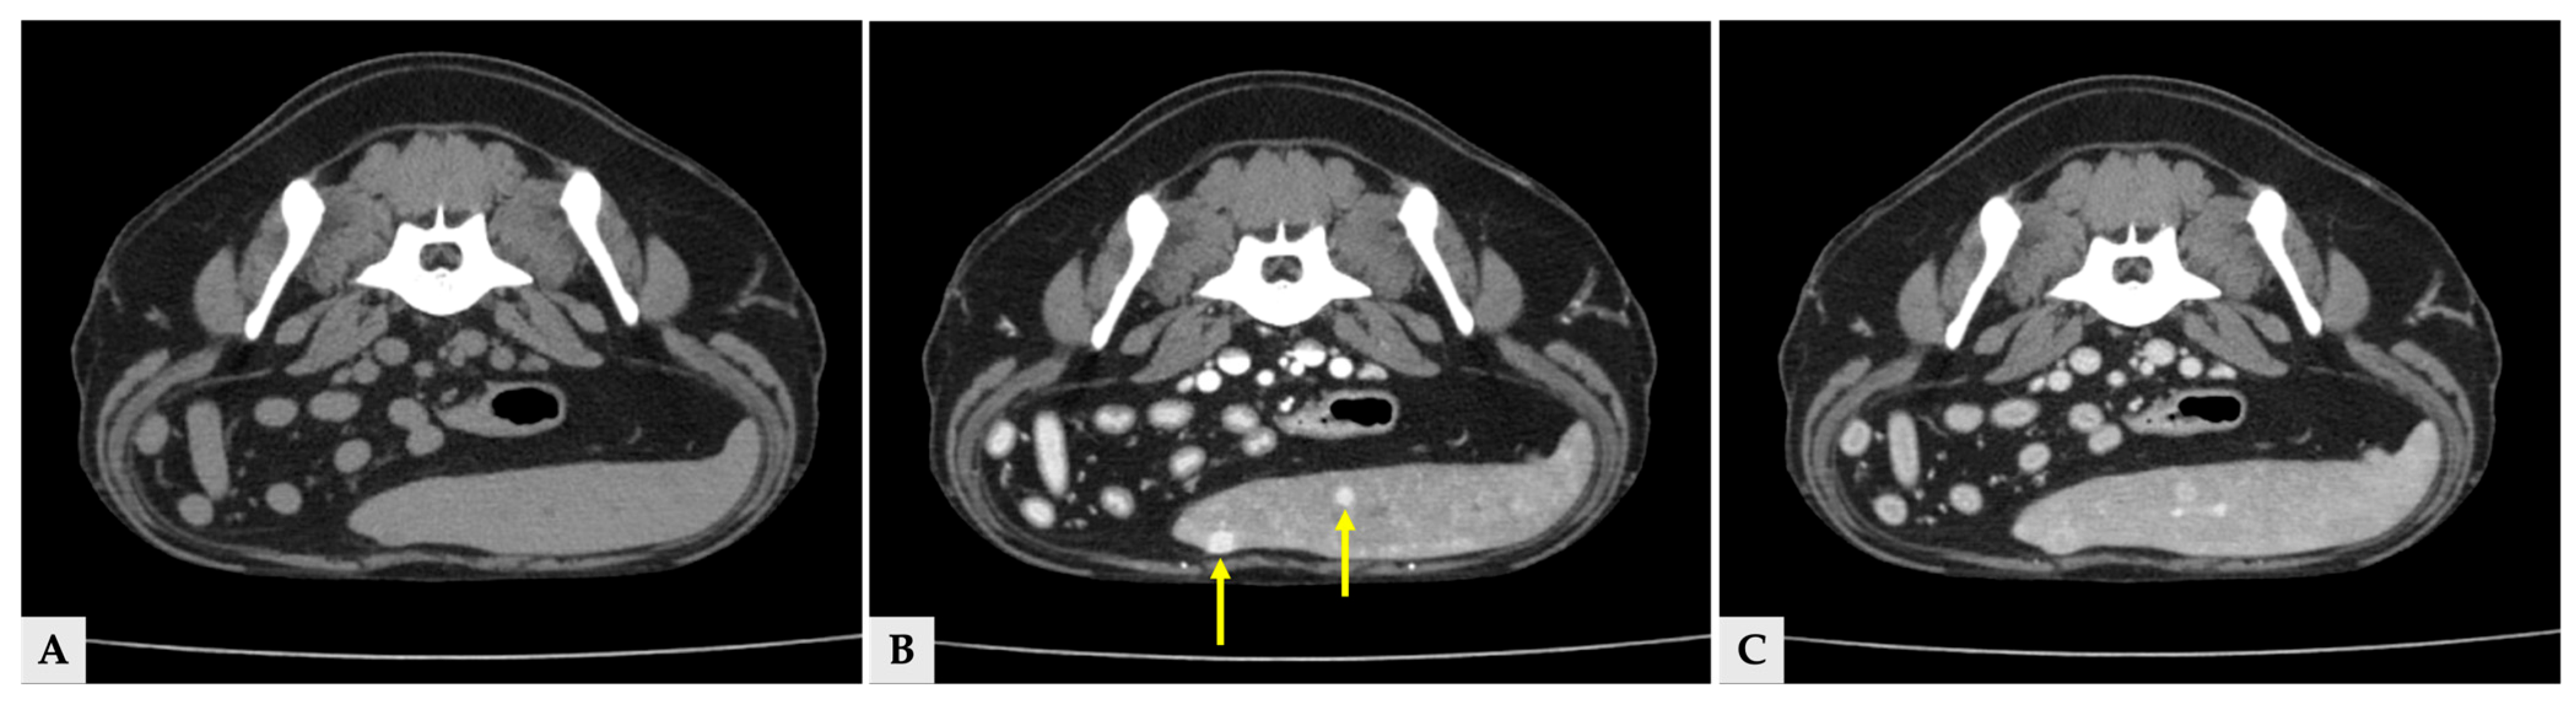

Multiple hyper- and hypoattenuating hepatic nodules were scattered throughout the liver parenchyma (maximum size 11.4 mm × 11.9 mm × 10.8 mm) (Figure 3), and numerous small splenic nodules exhibiting on pre-contrast and portal phase were also observed (Figure 4). Additionally, a soft-tissue mass was detected at the esophagogastric junction. Cervical ultrasonography revealed three distinct, heterogeneous right thyroid masses, with the largest mass demonstrating prominent vascularity on Doppler evaluation (Figure 5).

Figure 3.

Transverse view of the CT images of several hepatic nodules at the same anatomical level. (A) Pre-contrast image showing a liver nodule with attenuation similar to the surrounding hepatic parenchyma. (B) Portal phase image at the same level demonstrating heterogeneous hyperattenuation (arrow) and hypoattenuation (arrowhead). (C) Delayed phase image at the corresponding level, in which the nodules show attenuation similar to the surrounding hepatic parenchyma. The yellow arrows in all three images indicate the same liver nodule (11.4 mm × 11.9 mm × 10.8 mm).